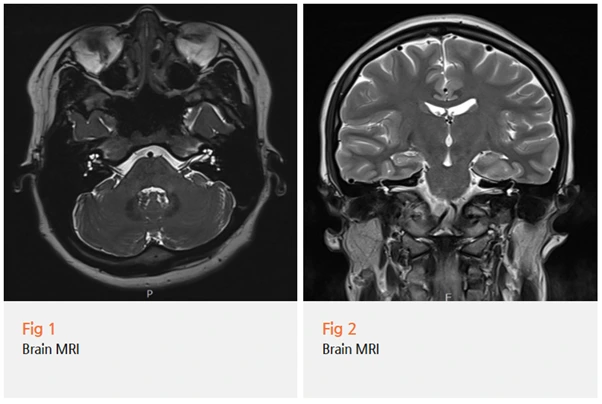

앞서 말씀드린 환자분도

증상 발생 즉시 내원하셨고, 저는 바로 검사를 제안했어요.

혹시 다른 위험한 병 때문에

마비가 온 건 아닌지 확인해야 한다며

뇌 MRI 검사를 하자고 말씀드렸죠.

다행히 이 환자분은 뇌 MRI 검사 결과

종양이나 다른 이상은 발견되지 않았어요.

환자분도 정말 안심하시더라고요.

"검사 결과 다른 이상은 없다고 하시니까 정말 안도가 됐어요."